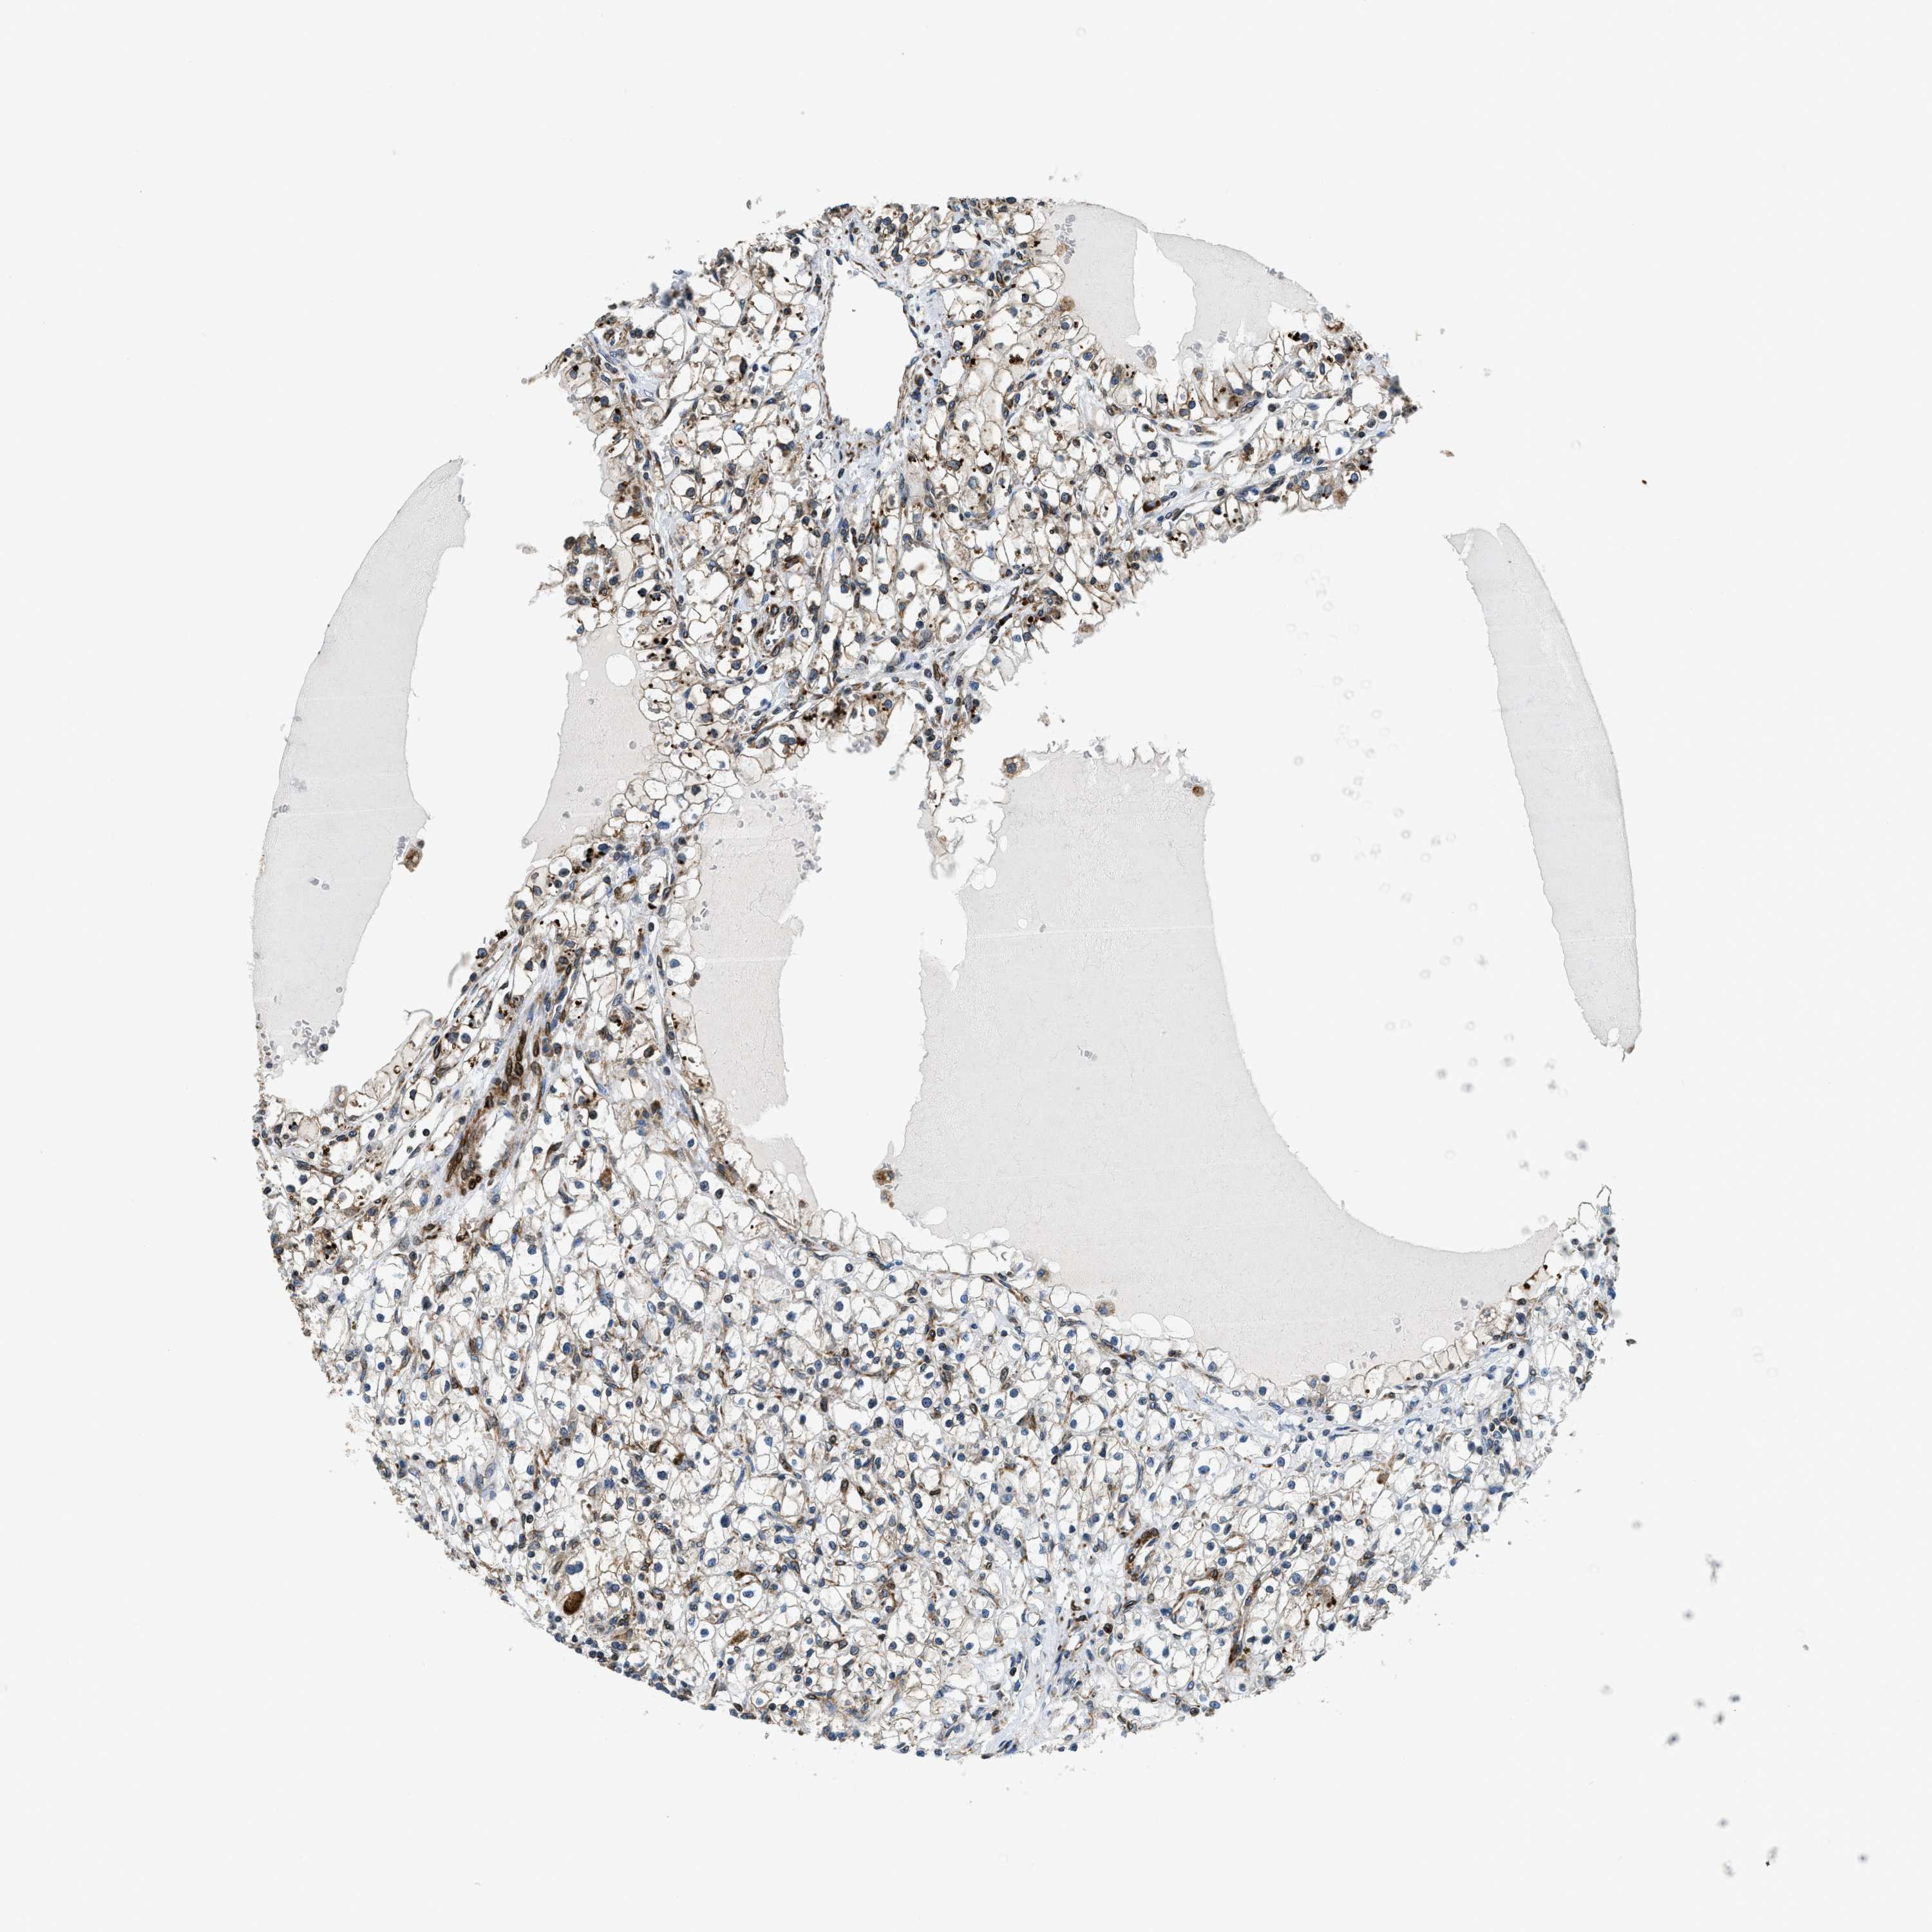

KIDNEY RENAL CLEAR CELL CARCINOMA (VALIDATION) - Interactive survival scatter ploti

The Survival Scatter plot shows the clinical status (i.e. dead or alive) for all individuals in the patient cohort, based on the same data that underlies the corresponding Kaplan-Meier plots. Patients that are alive at last time for follow-up are shown in blue and patients who have died during the study are shown in red.

The x-axis shows the expression levels (FPKM) of the investigated gene in the tumor tissue at the time of diagnosis. The y-axis shows the follow-up time after diagnosis (years). Both axes are complimented with kernel density curves demonstrating the data density over the axes. The top density plot shows the expression levels (FPKM) distribution among dead (red) and alive patients (blue). The right density plot shows the data density of the survived years of dead patients with high and low expression levels respectively, stratified using the cutoff indicated by the vertical dashed line through the Survival Scatter plot. This cutoff is automatically defined based on the FPKM cutoff that minimizes the p-score. The cutoff can be changed by dragging the vertical line or by entering a cutoff value in the square labeled "Current cut-off".

Under the Survival Scatter plot the p-score landscape (black curve; left axis) is shown together with dead median separation (red curve; right axis). Dead median separation is the difference in median mRNA expression between patients who have died with high and low expression, respectively. It is calculated as follows: median FPKM expression of dead patients with high expression - median FPKM expression of dead patients with low expression. This is intended to aid the user in visually exploring custom cutoffs and the associated p-scores and dead median separation.

Individual patient data is displayed and can be filtered by clicking on one or more of the category buttons on the top of the page. Categories describing expression level and patient information include: high, low, alive, dead, female, male and tumor stages. The scale of the x-axis can be toggled between linear and log-scale by clicking on the "x log" button. Mouse-over function shows TCGA ID, patient information and mRNA expression (FPKM) for each patient.

& Survival analysisi

Kaplan-Meier plots summarize results from analysis of correlation between mRNA expression level and patient survival. Patients were divided based on level of expression into one of the two groups "low" (under cut off) or "high" (over cut off). X-axis shows time for survival (years) and y-axis shows the probability of survival, where 1.0 corresponds to 100 percent.

CDS2 is validated prognostic, high expression is favorable in Kidney Renal Clear Cell Carcinoma (validation)

Best expression cut offi

Based on the FPKM value of each gene, patients were classified into two groups and association between prognosis (survival) and gene expression (FPKM) was examined. The best expression cut-off refers the FPKM value that yields maximal difference with regard to survival between the two groups at the lowest log-rank P-value. Best expression cut-off was selected based on survival analysis .

When clicking on this number, the vertical dashed line indicating cut-off, the interactive survival plot, and the Kaplan-Meier curve will be adjusted to show results based on the best expression cut-off.

: 22.2

TCGA RNA samplesi

RNA-seq data is reported as average FPKM (number Fragments Per Kilobase of exon per Million reads), generated by the The Cancer Genome Atlas (TCGA) .

Normal distribution across the dataset is visualized with box plots, shown as median and 25th and 75th percentiles. Points are displayed as outliers if they are above or below 1.5 times the interquartile range. FPKM values of the individual samples are presented next to the box plot.

Average pTPM 18.0

Number of samples 100